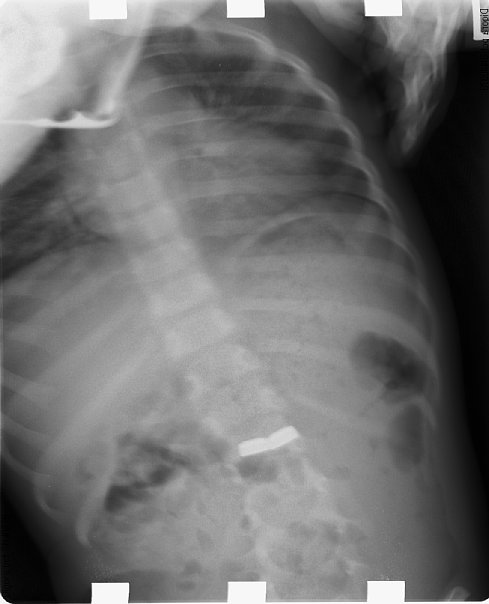

再び医院にとって返し、騒ぐ息子を無理矢理押さえつけて腹部のレントゲン写真を撮ってみました。

副鼻腔撮影用の条件設定なのでややフォーカスが甘いですが、どうやら胃の中に電池がありそうです。しかも2個。